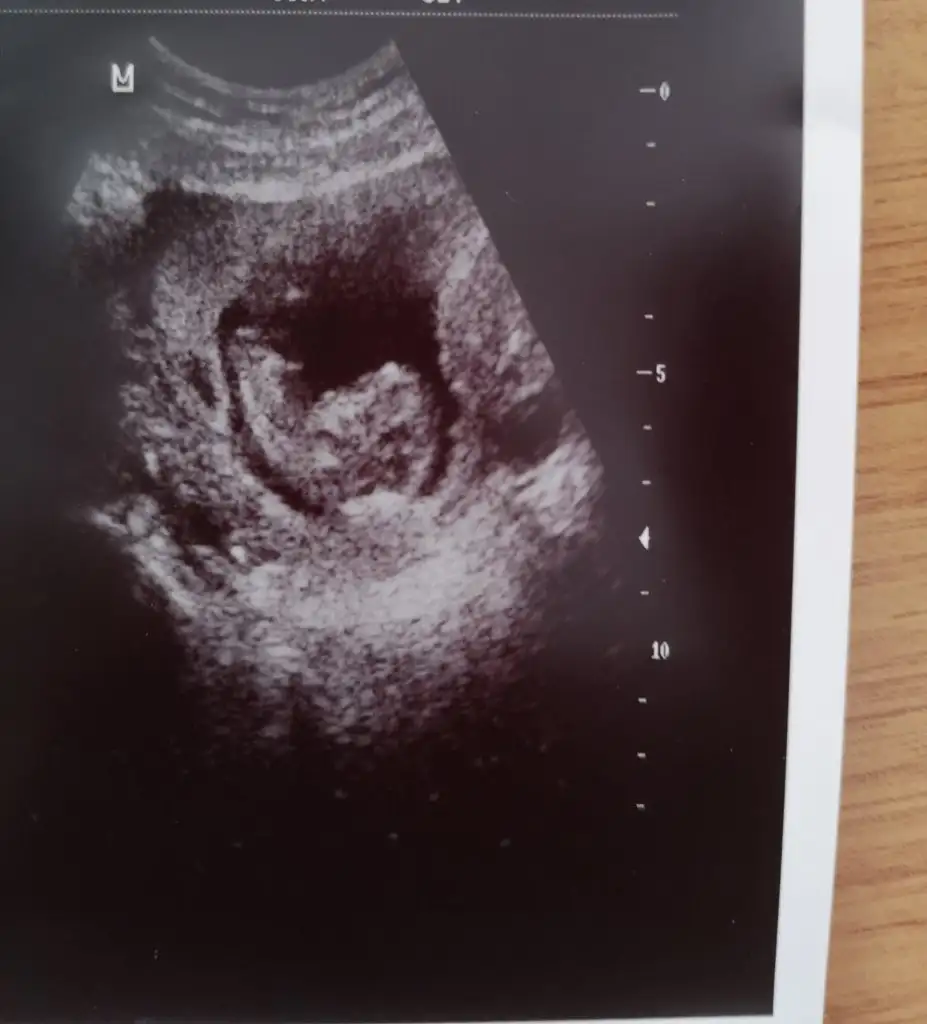

16+2 burda görüntü

@sip_sevdi bakın USG istemisimNuhu karşıya bakıyor kız gibi geldi bana başka USG varsa paylaşın 11 12 13 haftalar olmalı

Kaç haftalık USG 11 12 13 haftalar olmalı sanki erkek gibi başka USG varsa paylaşınMerhaba bunada bakabılırmısınız

Bu usg 11+4 haftalık , haftaya gidecegım cıbsıyet ogrenmeye 16 haftalık oluncaKaç haftalık USG 11 12 13 haftalar olmalı sanki erkek gibi başka USG varsa paylaşın